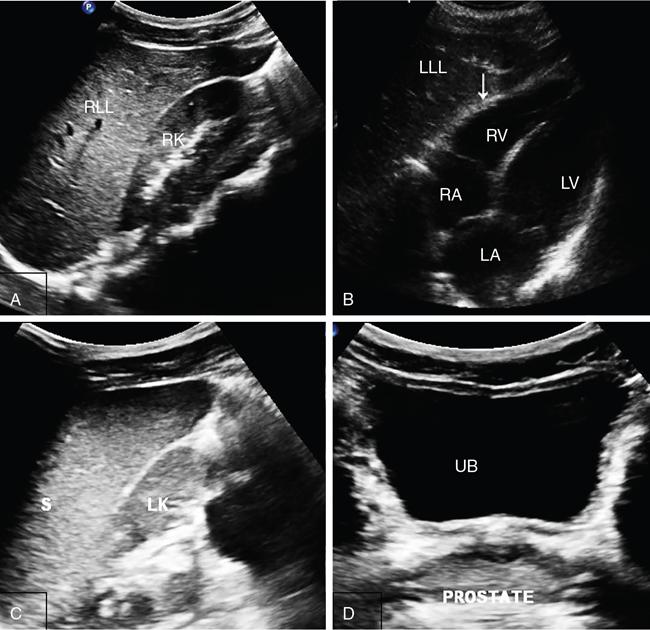

Amandeep Singh Trauma is one of the leading causes of morbidity and mortality. Blunt abdominal trauma accounts for 5% of trauma-related mortality and also contributes to 15% mortality polytrauma related mortality. More than 90% of the injuries are minor injuries and can be conservatively managed. In 10% of patients, serious injuries occur, like vascular bleeding, grade 4 or higher injuries of visceral organs, pseudoaneurysm formation, contrast or pelvicalyceal system (PCS) injury, all these require active intervention. Acute cause of death is mainly due to vascular bleed. Most common visceral organ affected in abdominal trauma is spleen followed by liver. The proper evaluation must be done of patient suffering from abdominal trauma. Abdominal trauma could be either penetrating or blunt. Blunt trauma occurs in patients of motor vehicle accidents, assault, falls and industrial accidents. Gunshot injuries and stab wounds lead to penetrating abdominal trauma. Many latest advances have been made in field of radiological imaging and imaging-guided interventional therapies, which enables nonsurgical management of haemodynamically stable patients with abdominal trauma. Contrast-enhanced computed tomography (CECT) is the investigation of choice for solid organ injures evaluation. Multidetector computed tomography (MDCT) can also help in detection of both vascular and visceral injuries following blunt abdominal trauma, for quicker examination. Thus, fast and accurate diagnosis plays a critical role in the management of patient. For appropriate care of patient imaging guideline has been recommended that includes (Fig. 7.14.1): So in haemodynamically unstable patients with blunt abdominal trauma we require: The chest X-ray erect is the earliest and most sensitive investigation for evaluation of pneumoperitoneum. With optimal radiographic technique and proper upright positioning of the patient for at least 10–15 minutes are required to detect even a small amount of air. It is possible to demonstrate up to 1.0 cc of free air on upright chest radiograph. However, plain radiographs of the abdomen are not the appropriate investigation of choice for the detection of haemoperitoneum. More than 800 cc volume of intraperitoneal blood volume is usually necessary for the demonstration of classic plain radiographic signs, for example ‘dog ear’ or ‘bladder ear’ sign when there is accumulation of intraperitoneal blood in the pouch of Douglas. Paracolic gutters are the most dependent intraperitoneal areas are where the collection of blood occurs which further displacing the right or left colon medially. The FAST is a technique for assessment of haemoperitoneum and hemopericardium (Figs. 7.14.1 and 7.14.3). It has sensitivity and specificity of more than 85% and 98%, respectively. Recently extended FAST (eFAST) protocol has come into the trauma algorithms. The eFAST examines each hemithorax for the presence of hemothorax. The FAST exam assesses the pericardial cavity and peritoneal spaces for fluid. The right upper quadrant (RUQ) evaluates the hepatorenal recess/Morrison’s pouch, the right paracolic gutter, the subdiaphragmatic area, and the caudal end of the left lobe of liver (Fig. 7.14.4a). Overall sensitivity for the detection of free fluid in the RUQ view is approximately 66%. Next is the subxiphoid (or subcostal) views to evaluate the pericardial space for any free fluid. Ultrasound detects as little as 20 cc of pericardial fluid and studies have shown excellent sensitivities and specificities approaching 100%. The subcostal view is to be required for differentiating pleural and pericardial. Left upper quadrant (LUQ) view is helpful to inspect the splenorenal recess, the subphrenic space, the left paracolic gutter and the left lower hemithorax during performing (eFAST). Similar views of the right hemithorax are obtained when scanning the RUQ. For each hemithorax view, probe has to be slide cranially above the diaphragm. The presence of the hyperechoic vertebral bodies, or ‘spine sign’, helps in identifying the fluid in the pleural cavities. US has sensitivity and specificity of 92%–100% in detection of hemothorax. Suprapubic view is beneficial in evaluating free fluid in the rectovesical pouch and cul-de-sac (rectouterine and vesicouterine) in males and females, respectively (Fig. 7.14.4b). There are no absolute contraindications to the eFAST. Curvilinear probe of frequency 2–5 MHz is used for the eFAST exam to reduce delays when switching between transducers. Likewise, the 5–12 MHz linear (or vascular) probe is ideal for assessing for pleural sliding. Although MRI does not play a role in the initial evaluation of blunt abdominal trauma. However, MRCP may be specifically useful in detecting biliary leaks. Angiographic embolization is needed when there is evidence of vascular injury (pseudoaneurysm, arteriovenous fistula) on CT scan and inactive contrast extravasation as an alternative to surgery. There is a great role of angiography in providing haemostasis in haemodynamically stable patients with high grade (IV and V) liver and spleen injuries. Computed tomography is now used as the principal imaging modality for diagnostic evaluation of abdominal trauma. It is useful in detecting both intraabdominal and retroperitoneal structure injuries and grading severity of specific parenchymal injury, along with evaluation of associated injuries of head and chest. Advantages of CT over DPL, includes detailed evaluation of injuries, associated haemorrhage and detection of any contrast extravasation. DPL has now almost become obsolete. Following a negative abdominal CT study using helical scanner, trauma patients can be discharged without a period of observation. Intravenous contrast bolus of 100–150 mL (350 mg of iodine per millilitre with total iodine load of 35–52.5 g) injected at a rate of 3–5 mL/s via 18–20 gauge cannula placed in a large peripheral vein is administered in all trauma patients. Single bolus injection method is widely used. A split bolus technique has also been proposed which has minimized the radiation exposure as a single acquisition is performed for evaluation of the abdomen. Oral contrast material for evaluating patients is no longer administered at most large trauma centres in the setting of blunt trauma. CT protocol includes portal venous phase images of the abdomen and pelvis, which are acquired at the interval of 65–80 seconds after the beginning of intravenous contrast material administration. Along with portal venous phase series, delayed phase (5–10 minutes after intravenous contrast material administration) images are necessary for patients within the amount of radiation delivered. Those with severe injury and those who have a displaced fracture of the pelvic ring, addition of an arterial phase (25–30 seconds after injection) of the abdomen and/or pelvis is required. Arterial phase helps in detection of vascular trauma that is not well appreciable on portal venous or delayed phases. With speed afforded by 64-detector scanners (and beyond), these CT angiograms can be comprehend protocols that use a single bolus of intravenous contrast material. CT cystography is done in patients suspected of bladder injury. It requires instillation of 300–400 mL of diluted water-soluble contrast material (40 mL of contrast in 360 mL of normal saline) into urinary bladder through a Foley catheter. In case of severe polytrauma, the CT cystography is done along with the delayed phase of the abdomen and pelvis which limits the radiation dose. However, it still requires full active distention of the bladder. Spleen is the most frequently injured organ following blunt abdominal trauma. Splenic injuries account for approximately 40% of all solid organ injuries occurring in abdominal trauma. Contributory factors include its potential for injury from fractured ribs, intraabdominal compression and its rich vascular supply. CECT abdomen is the modality of choice for imaging splenic injuries. Spleen shows heterogeneous enhancement on arterial phase and hence can simulate injury. So, the images should be obtained in portal venous phase. If there is dense contrast pooling seen within or around spleen, delayed CT images should be obtained to differentiate active bleeding from posttraumatic vascular injuries. Active bleeding retains the same density or even may increase in attenuation in delayed phase. Delayed phase may also be useful in differentiating a laceration from a splenic cleft. A cause of the potential inaccuracy of CT is the entity of delayed splenic rupture. Delayed splenic rupture can occur up to 48 hours after blunt trauma which should be differentiated from delayed presentation of splenic rupture due to a minor injury. On contrast-enhanced CT, splenic lacerations appear as linear low-attenuation defects within the splenic parenchyma. Shattered spleen may result due to combination of complex interconnecting lacerations. Intrasplenic haematomas appear as more diffuse hypo-attenuating regions. Splenic infarcts appear as triangular peripheral nonenhancing regions and must be distinguished from splenic haematomas. Subcapsular haematomas may occur alone or in combination with other injuries and result in low-attenuation collections that indent the splenic margin. The various CT manifestation of splenic trauma are: